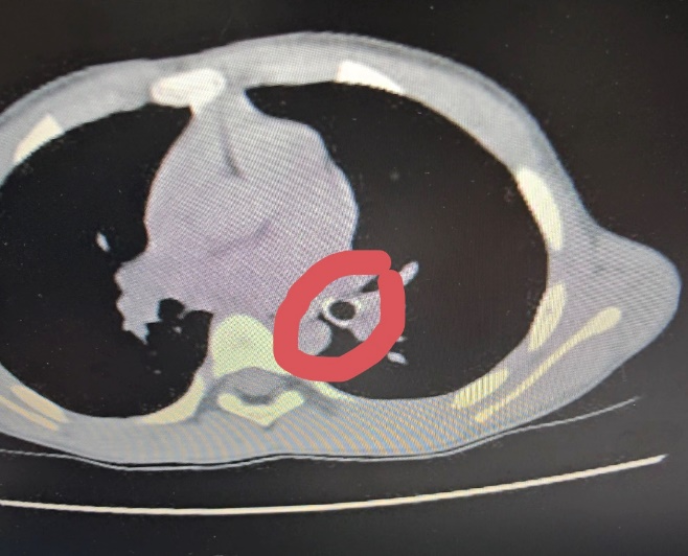

Qua thăm khám lâm sàng, các bác sĩ nghi ngờ trẻ hóc dị vật đường hô hấp, khả năng là đầu ngòi bút. Bệnh nhi được chỉ định chụp CT ngực, kết quả ghi nhận dị vật hình ống, bề dày thành khoảng 1,8mm, chiều dài khoảng 18mm, nằm tại phế quản thùy dưới trái, gây cản trở thông khí.